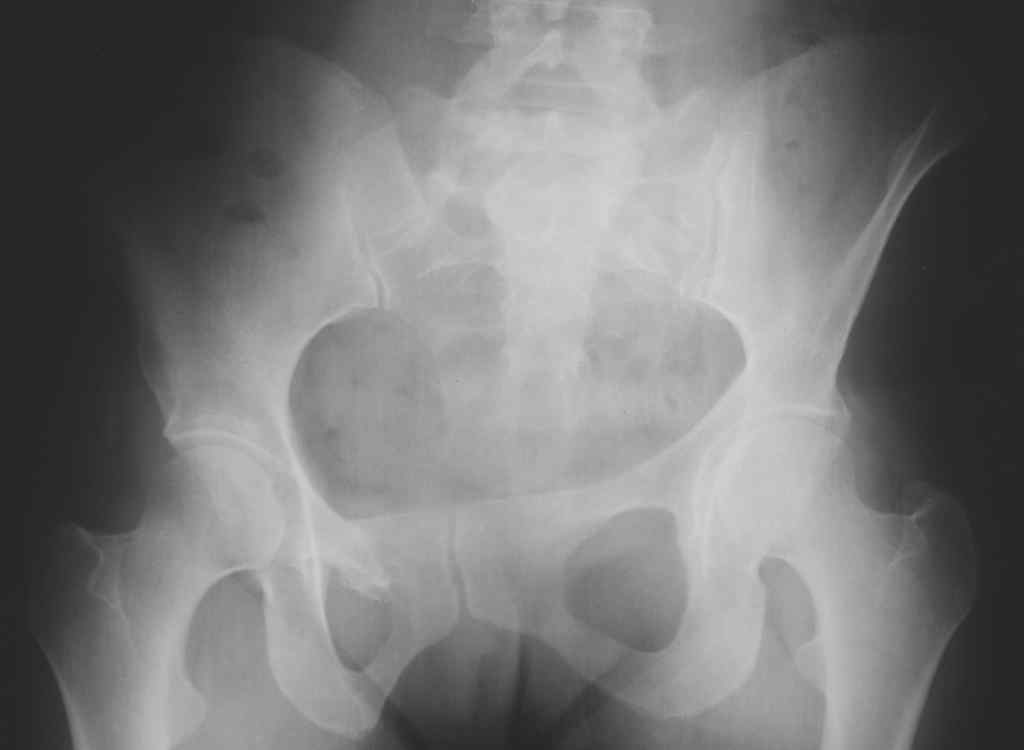

13/03/03 |  13/03/03 |  13/03/03 |  15/09/06 |  15/09/06 |  07/03/07 |  07/03/07 |  19/12/06 | К нам в клинику поступила пациентка 30 лет с диагнозом: Постравматическая ротационная стабильная деформация тазового кольца. Относительное укорочение левой н\конечности на 1 см. Левосторонний компенсаторный сколиоз 2 ст. Болевой синдром. травма автодорожная в январе 2003г. Пассажирка переднего сидения ваз 2109. лечились положением по Волковичу. С марта 2003 года жалуется на боли в тазу, ппояснице усиливающиеся при движении.В настоящее время жалобы на боли в области крестца, КПС больше слева, в пояснично-крестцовом отделе позвоночника. неприятные ощущения, щелчок при выпрямлении правого тазобедренного сустава из положения полного сгибания. боли в тазу появляются при ходьбе ч\з 100 м, так же при вставании из положения сидя, после сидения в течении 2-3 часов. при ходьбе более 100 м появпяется зябкость стоп больше справа. ходит при помощи трости в правой или в левой руке. без трости боли появляются сразу после начала ходьбы. пальпация болезненна в паравертебральных точках средне-грудного и пояснично-крестцового отделов позвоночника, КПС с обеих сторон. Объем движений в тазобедренных суставах полный.правый КПС заблокирован. симптомы натяжения с обеих сторон отрицательны.С 2003г. лечится консервативно, получала ЛФК, массаж, физиолечение - без эффекта. в 2005г. лечилась в санатории с ортопедическим уклоном, получала плавание в минеральной воде, магнитотерапия, массаж, ЛФК. отмечала умеренное улучшение в течении 2 недель.Вопросы:надо ли оперировать, т.е. устранять относительное укорочение левой н\конечности и как?Если не оперировать, то как лечить консервативно?Р-граммы, КТ прилогаются.

Проблема Вашей пациентки находится на границе интересов специальностей ортопедия (вертебралогия) и неврология (нейрохирургия), вероятно, поэтому так мало откликов на ваше обращение. Представленные рентгенограммы не все информативны (особенно спондилограммы от сентября 2006 года). Вероятно, необходимы дополнительные методы исследования к.т. МТГ, ЯМРТ, миелография.

Уважаемый Алексей. Описанные Вами клинические проявления указывают на нестабильность левого крестцово-подвздошного сочленения. Такие больные встречаются не редко (за последние 6мес.в нашей клинике оперировано 3 больных со сроками давности от 6мес. до 1 года). К сожалению рентгенологически их трудно обьективизировать. На КТ это проявляется артрозом и костными разрастаниями КПС. В Вашем случае рентгенограммы и представленные томограммы ничего не дали. Можно попробовать посмотреть связочный аппарат КПС на МРТ хотя не уверен что Вы получите окончательный ответ. Если Вы будете убеждены в этом диагнозе то выход один костно-пластический артродез левого крестцово-подвздошного сочленения с фиксацией канюлированными шурупами. Заманчиво конечно и устранить ротационное смещение половины таза, но это на Ваше усмотрение.

почему она должна возникнуть? Сломан вроде крестец, хотелось бы посмотреть функциональные снимки таза.

Уважаемый Максим. Снимки от 7.03.07 и есть функциональные, т.е. стоя на правой, и левой ноге.